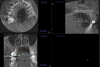

Other kinds of artifacts that are related to the CBCT technology itself may be present and compromise image quality, sometimes rather significantly.7 These artifacts are an inherent problem of CBCT and medical computed tomography because their appearance is a product of the reconstruction algorithms employed to compose the digital CBCT and CT images. In addition, the presence of any radiopaque materials is a frequent cause of artifacts. Metallic dental restorations, fixed prostheses, posts, and even gutta-percha may create artifacts that can obscure the visualization of the region of interest (Figure 3). As a result, fine diagnostic tasks may be impossible in proximity to restorations with high radiopacity. A number of CBCT manufacturers currently offer artifact reduction applications. These seem to have improved the resulting image quality; however, any possible gain in diagnostic efficiency has yet to be determined (Figure 4).

Beam hardening is another type of image artifact that is closely linked to the metallic artifact in CBCT images. These are dark, linear or cup-like bands near metallic restorations or implants, which may mimic osseous defects around dental implants or dental caries around restorations. Sometimes, their existence in combination with metallic artifacts in a heavily restored dentition may severely affect image quality to the degree that close anatomical structures like the crest of the alveolar ridge may be completely obscured. If fine detail is of the essence, in order to avoid metallic artifacts, it is sometimes advisable to remove any large restorations or posts from the teeth prior to scanning (if there was a plan to replace the restoration). Other times, increasing the slice thickness of the respective sections will reduce the deteriorating effects of the beam hardening and metallic artifacts.

(3.) A CBCT coronal section of the maxillary sinuses showing severe metallic artifacts (horizon- tal, bright in appearance bands) originating from the crowns of the maxillary and mandibular teeth.

Figure 3